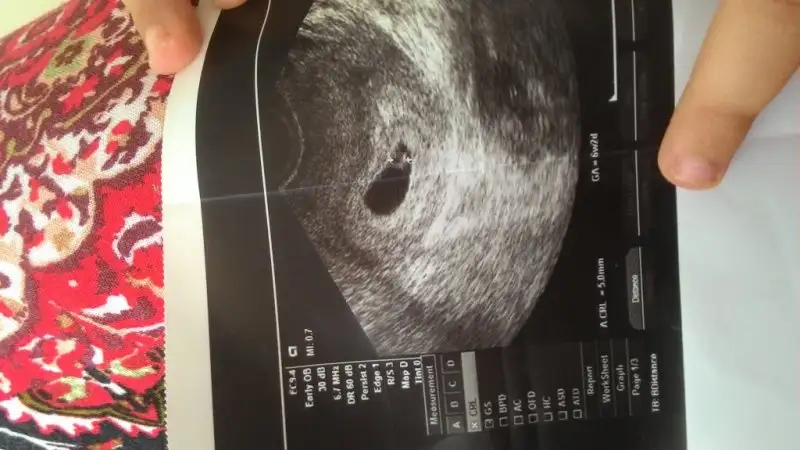

Ramzi Teorisi ve cinsiyet tahmini ( tutma olasılığı %85 miş )

bunuda yorumlarmisiniz

Benim de solda ama bugün öğrendim ki kız bu tutmadı bende :) bir tek cin takvimi tuttu ve ben hep kız hissediyordum allah gönlüme gore verdi

Senin plasenta solda miydi cnm,foto varsa at.benimde 2.kızımda kızım kesenin sağındaydı plasenta soldaydı kızımda bende de tutmadı.bak fotosu